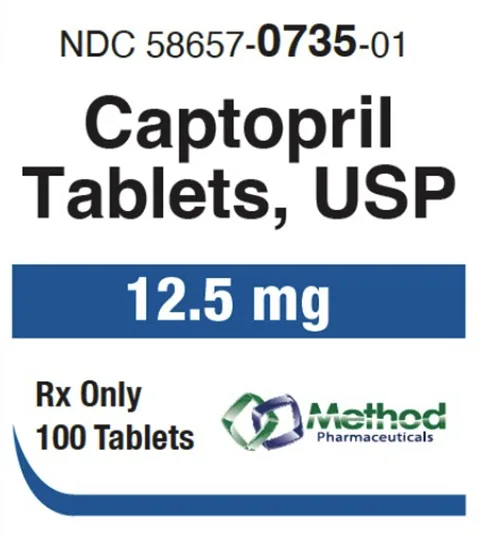

Featured products

Ready to deliver better care?

Explore our extensive range of cost-effective alternatives to popular medications tailored for your pharmacy.